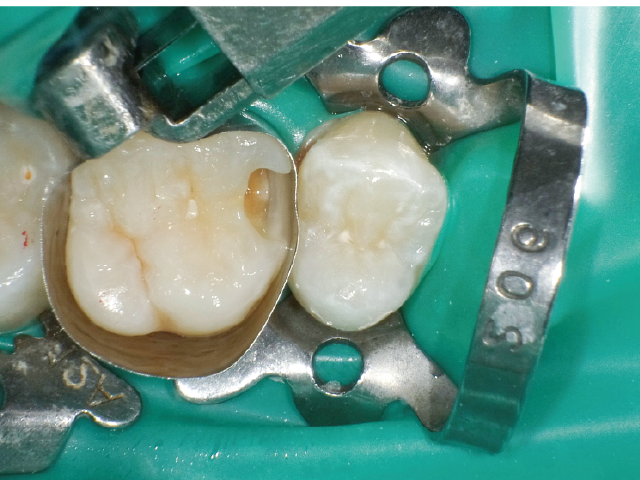

①窩洞形成段階(図1~7)

本症例では、ダイヤモンドの微粒子でコーティングされたエアースケーラーチップを窩洞形態の仕上げに使用。隣在歯の誤切削を防止し、エナメル質の切削断面を歯肉側窩縁までなめらかになるよう仕上げました。

本チップは切削時にストレスが少ない穏やかな振動のエアースケーラー専用のダイヤモンドチップで、切削部となる半球形状の面にのみダイヤモンド砥粒がコーティングされており、背面平坦部は隣在歯を削らないよう平滑になっています(図8、9)。チップの屈曲角度は110°に設定され、窩洞へのアクセスが容易な形状となっています。S67D(アングルの外側)、S68D(アングルの内側)チップは半球状の切削部位が設定され、臼歯部の近遠心両側の窩洞形成に使用が可能です。本症例では、左上6近心隣接面部の窩洞であったため、アングルの外側に半球状の切削部位が設定されている「S67D」を使用しました。これらの器具を使用することにより、頬舌側の隅角部歯質を温存した最小限の規模で窩洞形成を終了、防湿操作および隔壁の設置に移行することができました。